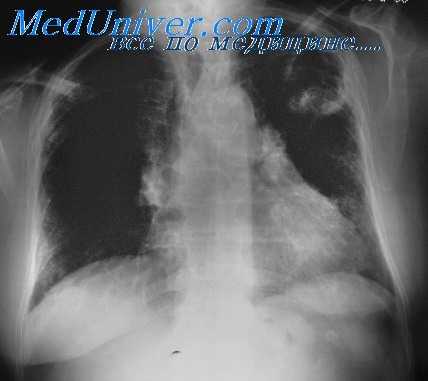

- Лучевая диагностика.Рентгенологическая картина в легких отличается разнообразием. Определяются нестойкие эозинофильные инфильтраты, плотные округлые или шаровидные тени с полостями распада, расположенные преимущественно в верхних долях лёгких, мелкоочаговая диссеминация. Характерным признаком аспергилломы является наличие серповидного просветления в полости округлого или овального образования, которое смещается при изменении положения тела (симптом погремушки). При заполнении полости аспергилломы контрастом грибные массы всплывают (симптом поплавка).

КТ ОГК. Полостное объемное образование в нижней доле правого легкого, частично заполненное грибковыми массами.